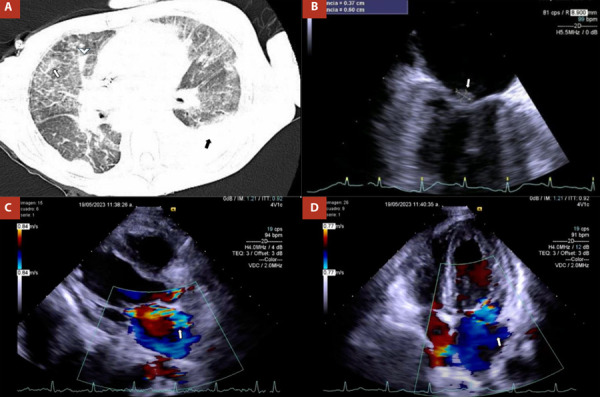

Infective endocarditis is a disease that affects mainly the endocardial surface of the heart and cardiac valves (native or prosthetic). The main risk factors for developing infective endocarditis are male sex, older age, intracardiac shunts, prosthetic valves, rheumatic, and congenital heart disease, intracardiac devices, intravenous drugs use, immunosuppression, and hemodialysis. Streptococci and Staphylococci spp. have been the most frequent isolated organisms. On the other hand, the most common fungal organism in infective endocarditis is Candida albicans (24-46%), followed by Aspergillus spp. (25%), and a few cases by Cryptococcus neoformans, which are associated with higher rate of mortality. This case provides an interesting case of Cryptococcus neoformans native valve infective endocarditis in a young woman with stage IV chronic kidney disease and severe malnutrition.